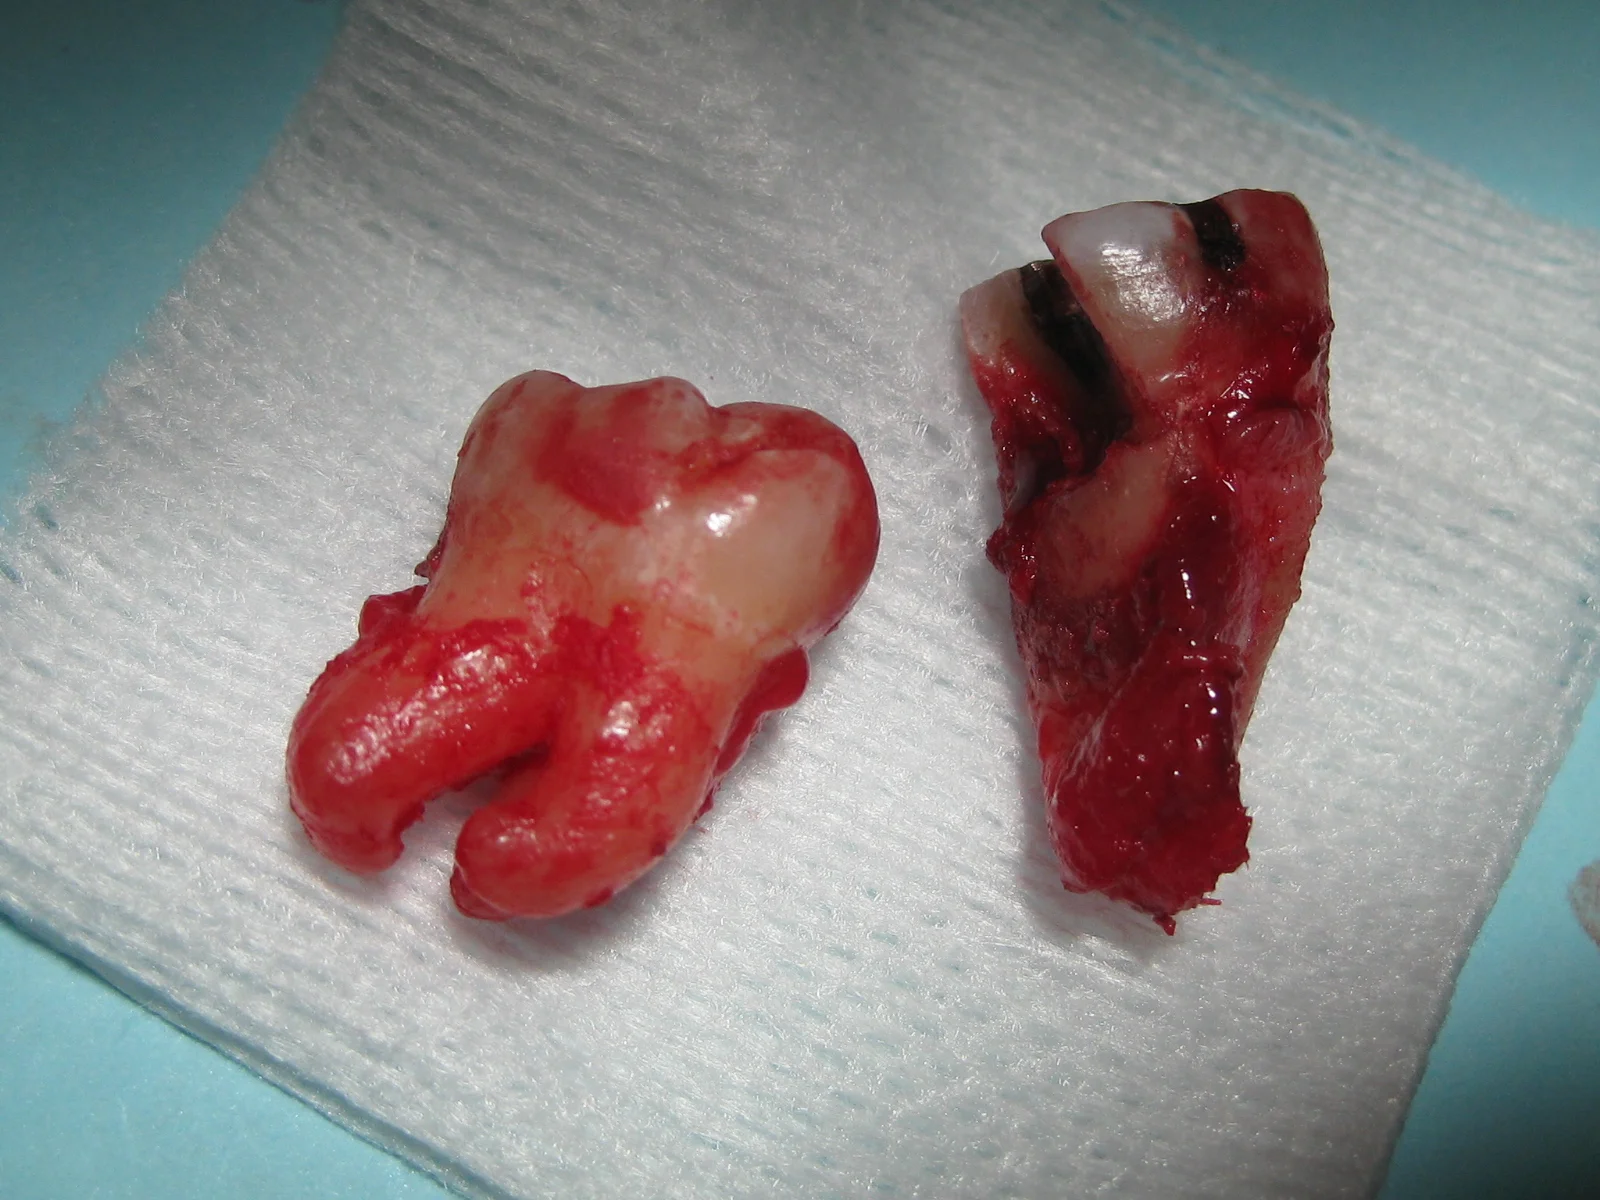

Our patient presented with a horrible tooth ache on her lower right molar.  It was hypersensitive to pressure. After a thorough exam, the tooth was fractured under the gums and couldn't be saved.  Our patient stated that this particular tooth had root canal treatment 3 separate times by 3 separate root canal specialists!  Everyone did everything they could to save the tooth, but it finally gave up and broke.  We carefully extracted the tooth and a bone graft was completed at the same time.  Immediate placement of the implant was not possible due to a horizontal defect of the bone and soft tissue.  After the bone graft healed, we placed the implant and delivered her new crown.  She is eating and living comfortably again!